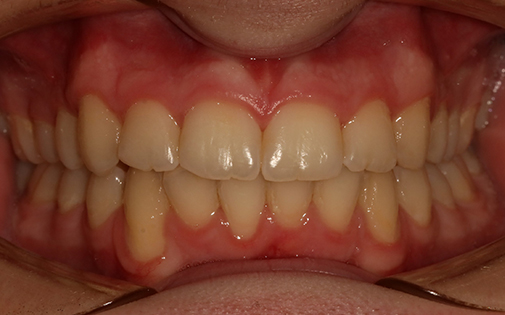

This patient had treatment with upper and lower fixed braces for just over 2 years. Despite the fact that his teeth were very crowded, he did not need any teeth removed.